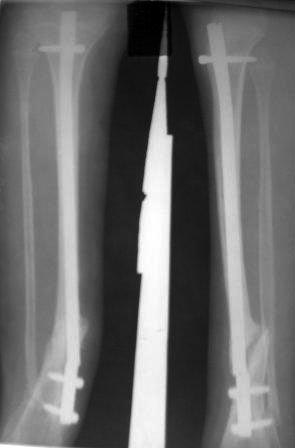

Уважаемые коллеги! помогите советом! Мальчик 2000 г.р. В 2007г получил перелом н/з костей правой голени, в районе лечили гипсом 6 месяцев, сращения нет, в обл.центре КДО аппаратом Илизарова - 3 месяца, после повторная деформация, в НИИТО КДО аппаратом Илизарова -7 месяцев, перелом якобы сросся, но после снятия аппарата через 2 недели после незначительной травмы повторный перелом. И родители начали лечиться у различных табибов и знахарей, мальчик не наступал, ходил с двумя костылями, одели различные ортезы и повязки, и нога сильно атрофировалась.(Мне кажется у ребенка был врожд. ложный сустав, латентная форма) , и в 2011 г, в октябре обратились к нам. , было произведена после рассверливания канала БИОС плечевым стержнем,но стержень пошел по мед.стенке дистального отломка поэтому остался некоторый вальгус(операция без ЭОП) ребенок через неделю начал самостоятельно ходить, клинически деформации нет, все обрадовались, выписали, повторно приехали только ч-з 1,5 года вот с такой деформацией, но ребенок ходит в школу, бегает, незначительно хромает, родители требуют исправить деформацию. Пока в голове один план: удалить стержень, закрытая остеоклазия, аппарат Илизарова из двух колец постепенная коррекция деформации, рассверливание к/м канала, БИОС плечевым стержнем (чуть длиннее), дистально по латеральному кортексу с использованием поллерных винтов и спиц. С уважением Абдурашид.